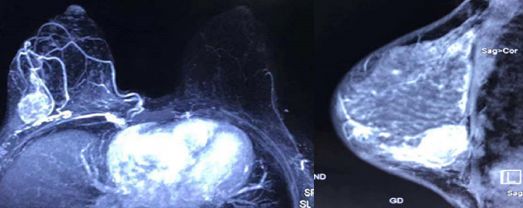

结合患者疾病的病理类型及患者本身体质状况不佳,与患者及家属反复商议,于2018年6月起采用术前新辅助内分泌治疗方案,具体方法为:氟维司群 500mg 肌注每28天同时联合阿那曲唑口服1mg qd。在新辅助内分泌治疗期间患者就诊于我院心血管内科积极对症处理以改善心脏功能,并行心脏瓣膜置换术。2018年12月完成内分泌治疗,综合疗效评估为完全缓解(complete response,CR,图2)。

图2 新辅助内分泌治疗后

患者于2019年1月行右乳腺癌改良根治术(breast cancer modified radical mastectomy),手术过程顺利,术后病理示:新辅助治疗后,左侧乳腺导管及纤维组织增生,部分导管扩张,局部泡沫细胞聚集,可见钙化,同侧腋窝淋巴结(0/17)未查见转移癌。结合术后病理结果,认为患者术前内分泌治疗已达病理学完全缓解(pathological complete remission,pCR)。后患者于2019年2月起口服阿那曲唑至今,期间定期复查未见明显转移与复发征象。